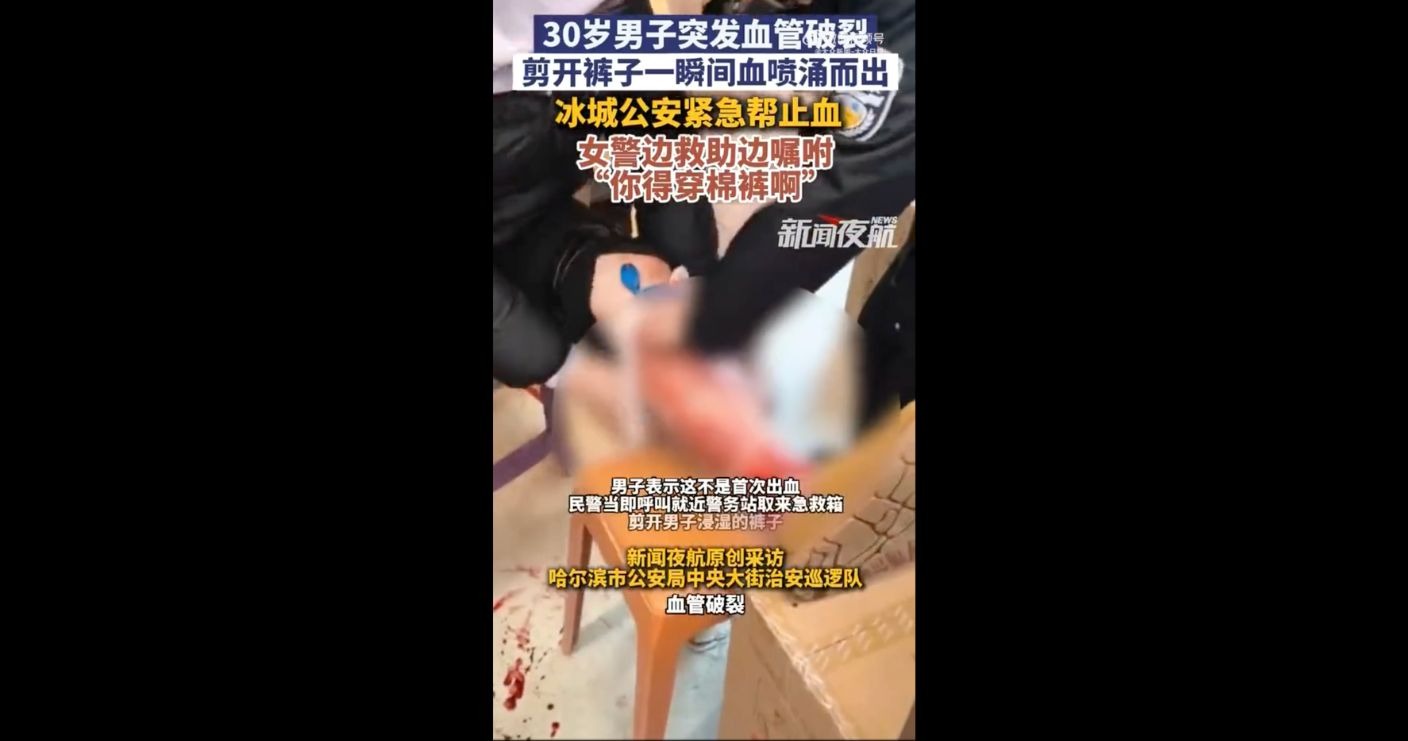

哈爾濱中央大街的巡邏警察日前在晚上7時多接獲女遊客求...